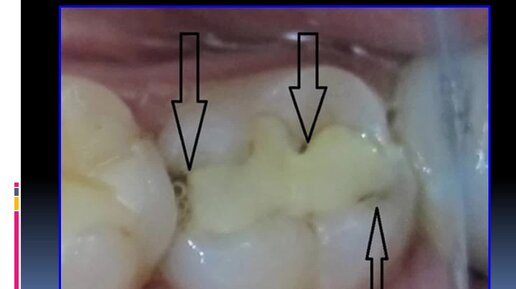

Secondary, atypical, multiple, blooming caries